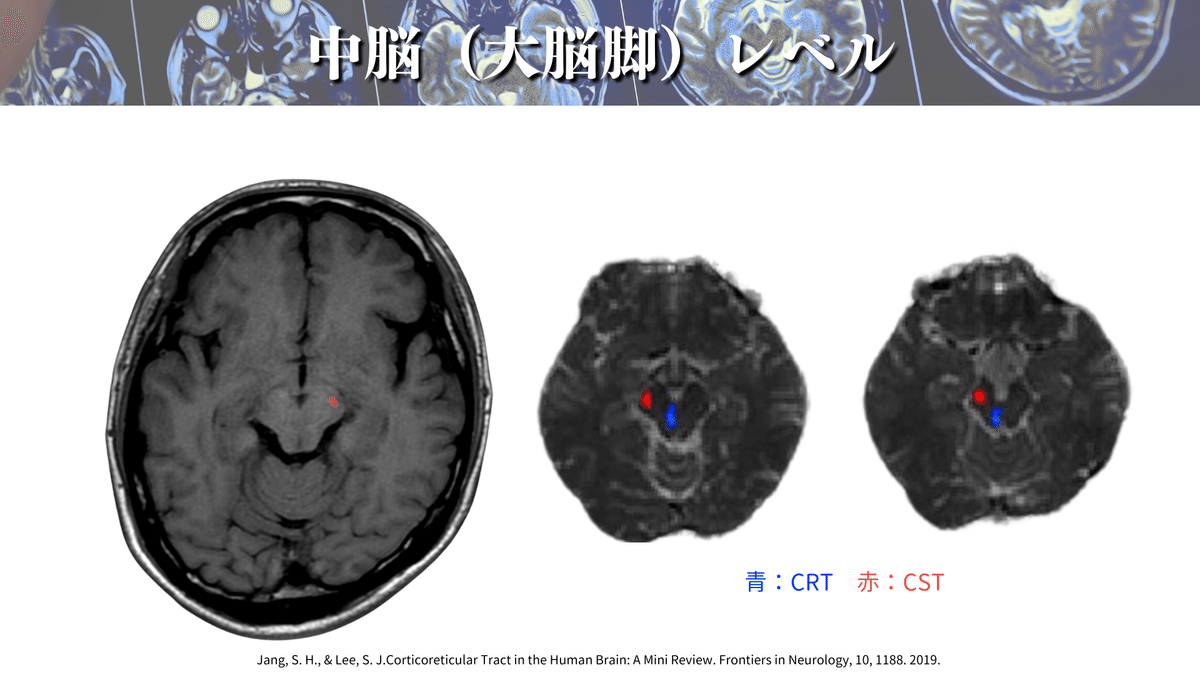

さらにこの論文では、上図のように拡散テンソルトラクトグラフィー(DTT)を用いてこれらの経路を視覚的に確認できる点が魅力です😍

CSTは大脳脚というところを通過していきます🏃♀️

大脳脚も詳しくみると大きく3ブロックになっていまして、内側が前頭橋路、中間が皮質延髄路とCST、外側が頭頂・側頭・後頭橋路が通るようです😳

DTTで確認をしても同様の場所を通過していますね👍(下図)

なので大脳脚では真ん中あたりを通っていると覚えると良いかもしれません☝️